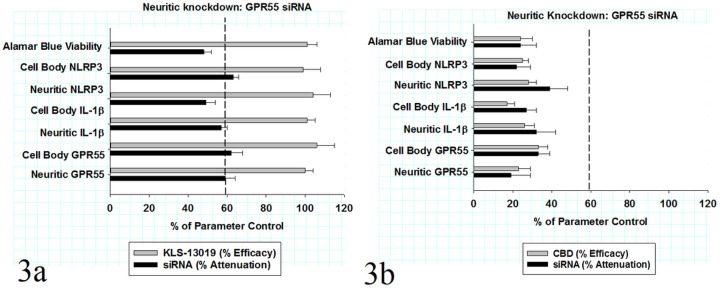

In all experiments to be described, a reversal paradigm was utilized to detect anti-inflammatory responses in DRG cultures that had been pre-treated for 8 hours with 3 μM paclitaxel to induced inflammatory responses (ref. Brenneman et al., 2022). After the inflammatory responses were established with paclitaxel pre-treatment, KLS-13019 was added to the cultures for additional 16 hours, followed by multi-analyte determinations of the DRG cultures. In addition to the inflammatory markers assayed in fixed cultures, all cultures were assessed before fixation with the viability dye alamar blue to measure possible toxicity and a loss of mitochondrial function (ref. Iuchi et al., 2019). As shown in Fig. 3a, a comparison is made between KLS-13019-mediated reversal from inflammation produced by paclitaxel (grey bars) and by the attenuation of that anti-inflammatory response produced by GPR55 siRNA (black bars). For each inflammatory response, the IR spot areas per neuron for GPR55, NLRP3 and IL-1b were determined in both neuronal cell bodies and the neurites. All of these data were expressed as per cent of control from their respective parameter control values. KLS-13019 was effective in returning all inflammatory assays back to their control levels. The concentration employed for these reversal assays was 100 nM KLS-13019, an amount that was a 10-fold excess to the minimum concentration required for a full anti-inflammatory response. In the black bars, the percent attenuation of the IR spot area for each inflammatory measures are shown for both cell bodies and neurites. The mean attenuation for all six of the inflammatory measures produced by GPR55 siRNA was very similar to one another and not significantly different from the overall mean response of all assays: 56 ± 3%. A dashed vertical reference line is provided to indicate the mean neuritic knockdown (59 ± 6%) of GPR55 IR area from controls. Thus, the attenuation of KLS-13019-mediated responses for anti-inflammatory markers corresponded closely to the knockdown of the neuritic GPR55 immunoreactive target area.

In addition to the inflammatory markers, KLS-13019 was fully effective in returning the Alamar blue viability values back to control levels. Further, the attenuation of KLS-13019-mediated protection from paclitaxel-induced toxicity was 63 ± 7%, a value similar to that observed for the inflammatory responses. Overall, these knockdown data are consistent with the conclusion that loss of IR area produced by siRNA in neurites had a corresponding effect on the efficacy of KLS-13019 in reversing inflammation and cellular toxicity. Together, these data suggest that GPR55 has a significant, if not dominant role in mediating these anti-inflammatory actions produced by KLS-13019.

GPR55 knockdown and responses to CBD

CBD, the naturally occurring substance upon which the structure of KLS-13019 was based, provided an important and arguably essential comparator on two levels: 1) the parent compound has anti-inflammatory properties based on the literature (ref. Costa et al, 2007; ref. Wang et al., 2023); and 2) CBD did not produce an effective reversal of mechanical allodynia in a mouse model of paclitaxel-induced neuropathic pain (ref. Foss et al., 2021). Thus, utilizing the same reversal paradigm described for KLS-13019, CBD mediated effects were measured with the same assays utilized for the new drug candidate. As shown in Fig. 3b, a comparison is made between CBD-mediated reversal of inflammation produced by paclitaxel (gray bars) and by the attenuation of that anti-inflammatory response produced by GPR55 siRNA (black bars). For each inflammatory response, the IR spot areas per neuron for GPR55, NLRP3 and IL-1b were determined in both neuronal cell bodies and the neurites. All of these data were expressed as per cent of control from their respective parameter control values. CBD was found to be effective in producing a significant effect on all inflammatory assays; however, the mean efficacy for all the assays was only 25 ± 2% of their respective controls. A dashed vertical reference line is provided again to indicate the mean neuritic knockdown of GPR55 IR area from controls: 59 ± 6% of control. In comparison, the mean cell body knockdown of GPR55 IR area was 21 ± 8% of control.

In addition to the inflammatory markers, CBD was only partially effective in returning the alamar blue viability values back to 24 ± 6% of the control level. Further, the attenuation of CBD-mediated reversal from paclitaxel-induced decreases was 24 ± 8% of control in the viability assay. Overall, these knockdown data are consistent with the conclusion that the efficacy of CBD in reversing paclitaxel-induced inflammation in the reversal paradigm was 4-fold less than that of KLS-13019. Furthermore, the amount of attenuation of CBD efficacy produced by GPR55 siRNA was less than half of that observed with KLS-13019 under the same experimental conditions.